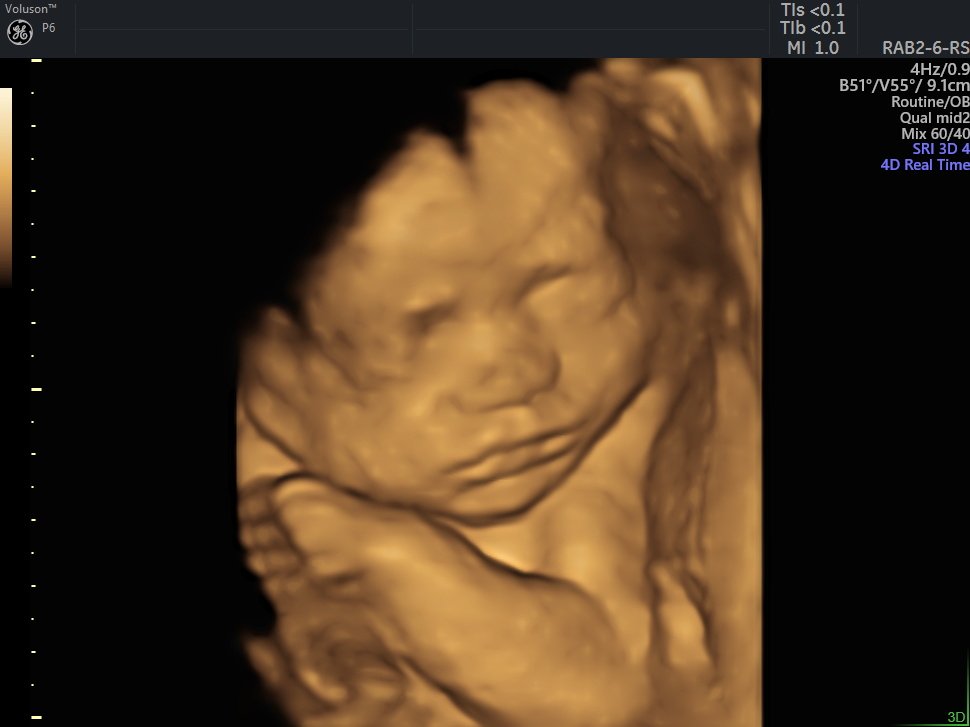

4 Boyutlu (Renkli) Ultrason ve Doppler Ultrasonografi

4 D Ultrasonografi